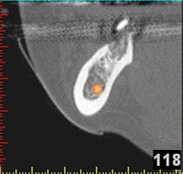

In komplexen Fällen, z. B. der Implantatversorgung eines kompletten Kiefers, oder bei schwierigen Knochensituationen bietet die 3-dimensionale Computerdiagnostik bzw. Planung und Durchführung erhebliche Vorteile und Sicherheit für den Patienten (siehe Bild 1 und 2).

Auf Basis einer computertomografischen (CT-) Kieferaufnahme ist eine dreidimensionale Darstellung der Knochen möglich. Der Zahnarzt kann dann am Computerbildschirm die Knochenqualität (z. B. Knochendichte) beurteilen und die optimale Position der Implantate im Vorfeld planen. Durch Verwendung spezieller Röntgenschablonen lässt sich auch die erwünschte Zahnstellung in die Planung einbeziehen. Die Simulation der OP erlaubt, das zu erwartende Ergebnis mit größtmöglicher Sicherheit vorherzusagen und dem Patienten am Bildschirm zu veranschaulichen.